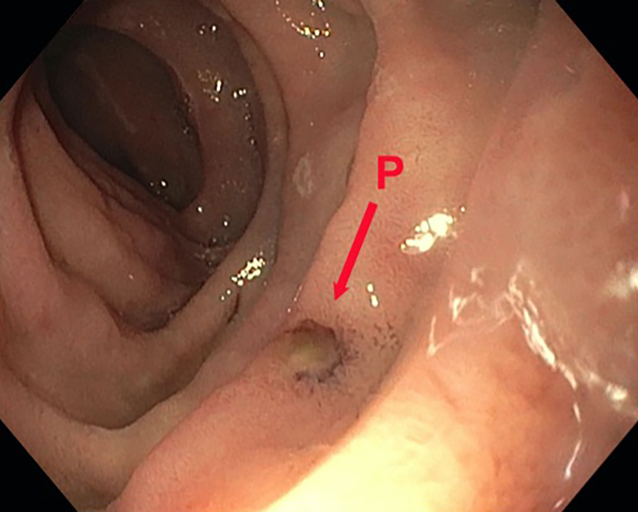

In the first endoscopic assessment after 3 days, normal, non-inflamed wound conditions were observed with a slight fibrin coating on the suture, without further signs of inflammation and no defect. Perfusion was good. The initial perifocal edema was regressing. The dOFD was not dislodged and was located with the drainage element in the duodenum. A new dOFD was placed endoscopically without any problems, and the preemptive therapy was continued for a second period (Fig. 4).

Fig. 4

Perforation defect (P) on postoperative day 4, drain change with inspection of the internal wound. There is no sign of bile imbibition in the wound; the biliary secretions have been completely suctioned off. The perforation site does not appear inflamed and has a minimal fibrin coating; no defect detectable